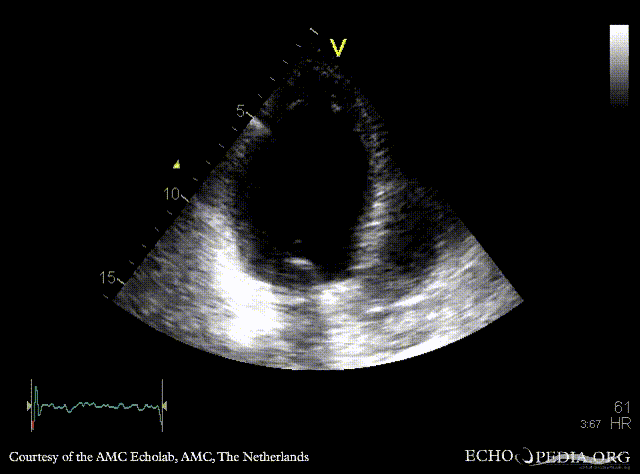

Infarction of posterior and inferior wall

PLAX: dilated left ventricle, akinesia of posterior wall PSAX: akinesia of posterior and inferior wall